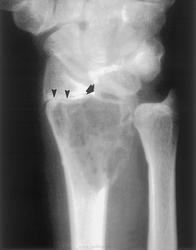

Гигантоклеточная опухоль.

Злокачественная гигантоклеточная  опухоль возникает из доброкачественной (частота 10-20%). После операции возможно появление рецидива опухоли.